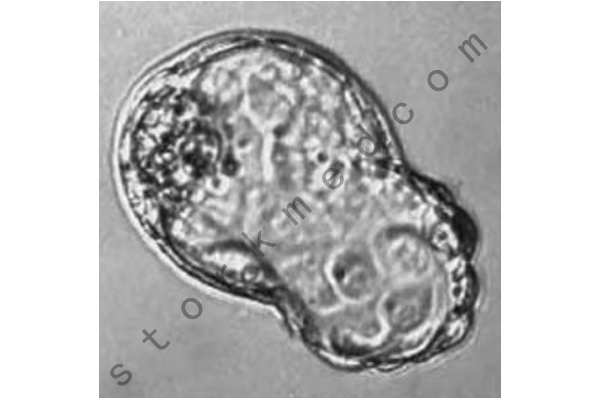

图8-桑葚胚(授精后约96小时)

桑葚胚由大约30个细胞(囊胚)组成,在大约96小时内形成,因为这些细胞只通过合子的分裂而产生,而且都在透明带内,透明带不能扩展,所以看不到内部细胞的生长。因此,每一个新细胞只有它所派生的细胞的一半大,而它的名字来自于与桑树叶的形态相似,因为它看起来像一个球形细胞的汇合体。